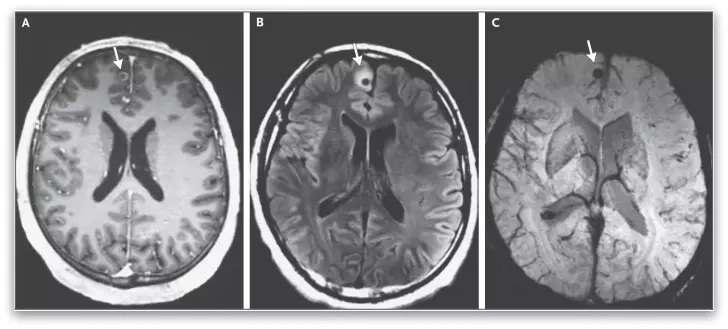

Скенирањето на мозокот откри три калцифицирани лезии. Со оглед на нивната презентација и медицинската историја на пациентот, лекарите заклучиле дека се работи за цисти кои припаѓаат на паразитската свинска тенија (Taenia solium). Овие црви слични на бели панделки се потпираат на човечките домаќини за да стигнат до фазата на возрасни од нивниот животен циклус, каде што се закачуваат за тенкото црево со десетици мали куки